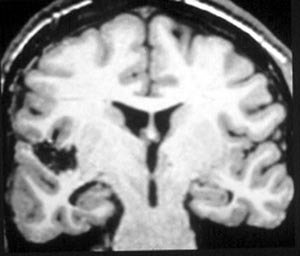

4b) Cavernoma

Figura 64 - Ressonância nuclear magnética pré-operatória.